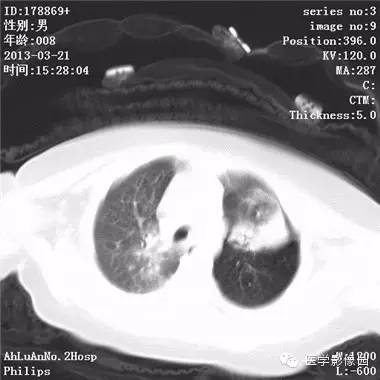

【病例】支气管异物1例CT影像表现

患儿男,8个月,呛咳,发热一周。实验室检查白细胞及中性粒细胞增高。

两肺肺纹理增多、增粗,右肺可见斑片状、片絮状模糊影,边界欠清;左肺上叶见楔形高密度影,内可见支气管征,尖端指向肺门;左肺下叶肺野透亮度增强;另见左肺主支气管内可见块状软组织密度影。

支气管异物(花生米)伴两肺炎症(追问病史,患儿奶奶层于一周前喂食患儿花生米,当时疑似“呛进去”,后来见好了也就没留意)。